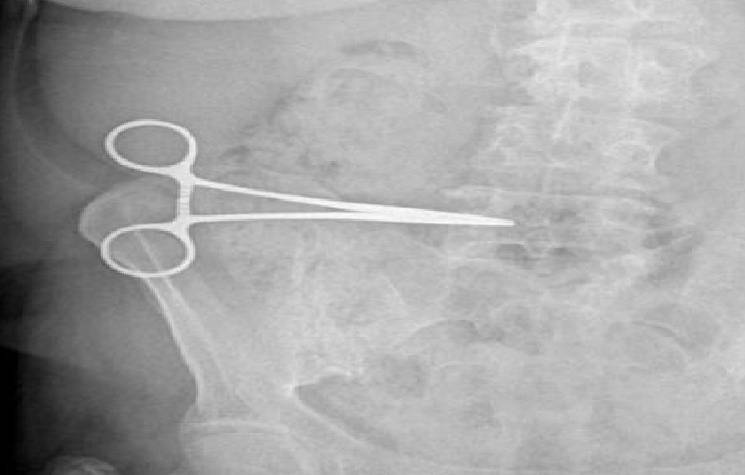

7 Yıl Sonra Fark Etti! Tam 16 Cm Boyutunda Makas Unutuldu

7 yıl önce kist ameliyatı olduğunu söyleyen Kala, ameliyatını yaptırdığı doktoruna giderek muayene oldu ve röntgen çektirdi. Röntgende çıkan sonuçlar ise şaşırtıcıydı! 16 cm boyutundaki bir makas vücudunda unutulmuştu. Ancak doktor acil ameliyat olması gerektiğini söyleyip sebebini belirtmedi.

Ameliyatını yapan doktorun tavırlarından şüphelenen Fatma Kala, ameliyatı kabul etmedi. KSÜ Sağlık ve Uygulama Araştırma Hastanesi’ne giderek durum hakkında bilgi verdi. Yapılan tetkiklerin sonucunda 16 cmlik makasın vücudunda unutulduğunu öğrendikten sonra doktoru hakkında suç duyurusunda bulundu.